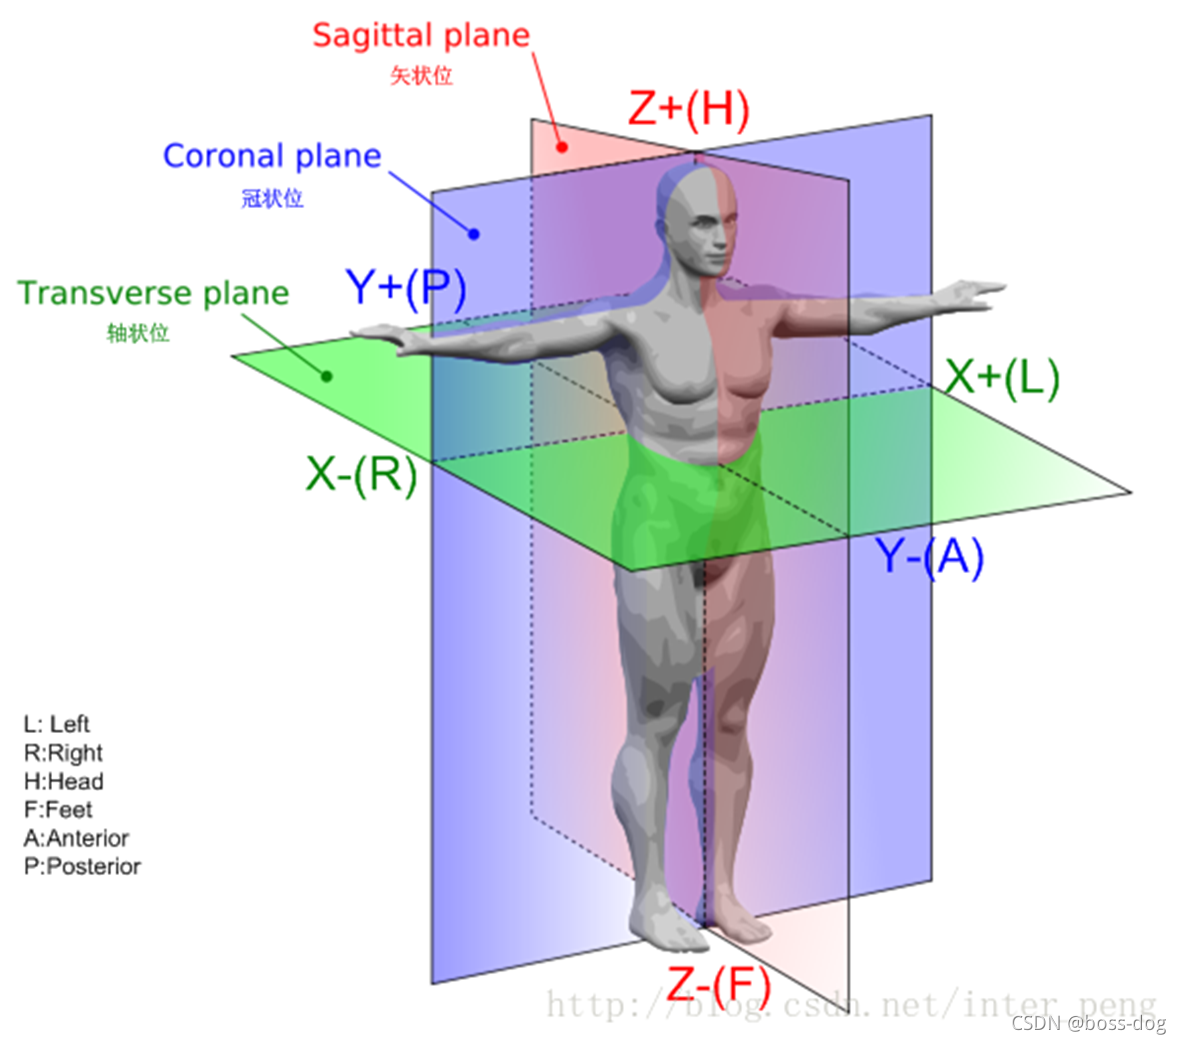

Image Orientation-1

DICOM3.0格式影像文件中和坐标有关的部分主要是以下几个数据元素:

- (0018,5100) Patient Position CS 1

- (0020,0032) Image Position (Patient) DS 3

- (0020,0037) Image Orientation (Patient) DS 6(用来表示斜着的轴状位、冠状位、矢状位)

- (0028,0030) Pixel Spacing DS 2(用来表示图片中每个像素所代表的X和Y水平方向和竖直方向的尺寸是多少、像素有多大)

- (0018,0050) Slice Thickness DS 1(用来表示切很多层,那每一层的厚度是多少)

Image Orientation-3

- (0020,0032) Image Position (Patient)描述了该张影像首个像素(“左上方”)的坐标,这个数据元素和(0020,0037)一起确定了该张影像中所有像素的坐标,用3个不超过16字节的字符串存放。分别是X,Y,Z值。

- (0020,0037) Image Orientation (Patient)是一个非常重要的数据元素。由6个不超过16字节的字符串存放。

在这里先要说明一下,在DICOM 3.0中坐标轴的指向完全以病人为准。以病人中心为原点,病人左手指向的方向为X轴正向,病人背后的方向为Y轴的正向,往病人头部的方向为Z轴的正向。因此是一个以病人为中心的右手坐标系。

Image Orientation-4

Image Orientation-5

(0020,0037) 的前三个数字代表分别代表行向量(行递增方向)和X,Y,Z轴夹角分别的余弦值(Cosine),后三个数字分别代表列向量(列递增方向)和X,Y,Z轴夹角分别的余弦值。这样就能精确计算出该张影像中每一个像素点在坐标系中的位置,对于多排螺旋CT产生的影像序列来说,这个意义尤其重大。

- 横断面:(1,0,0)(0,1,0)

- 冠状面:(1,0,0)(0,0,-1)

- 矢状面:(0,1,0)(0,0,-1)